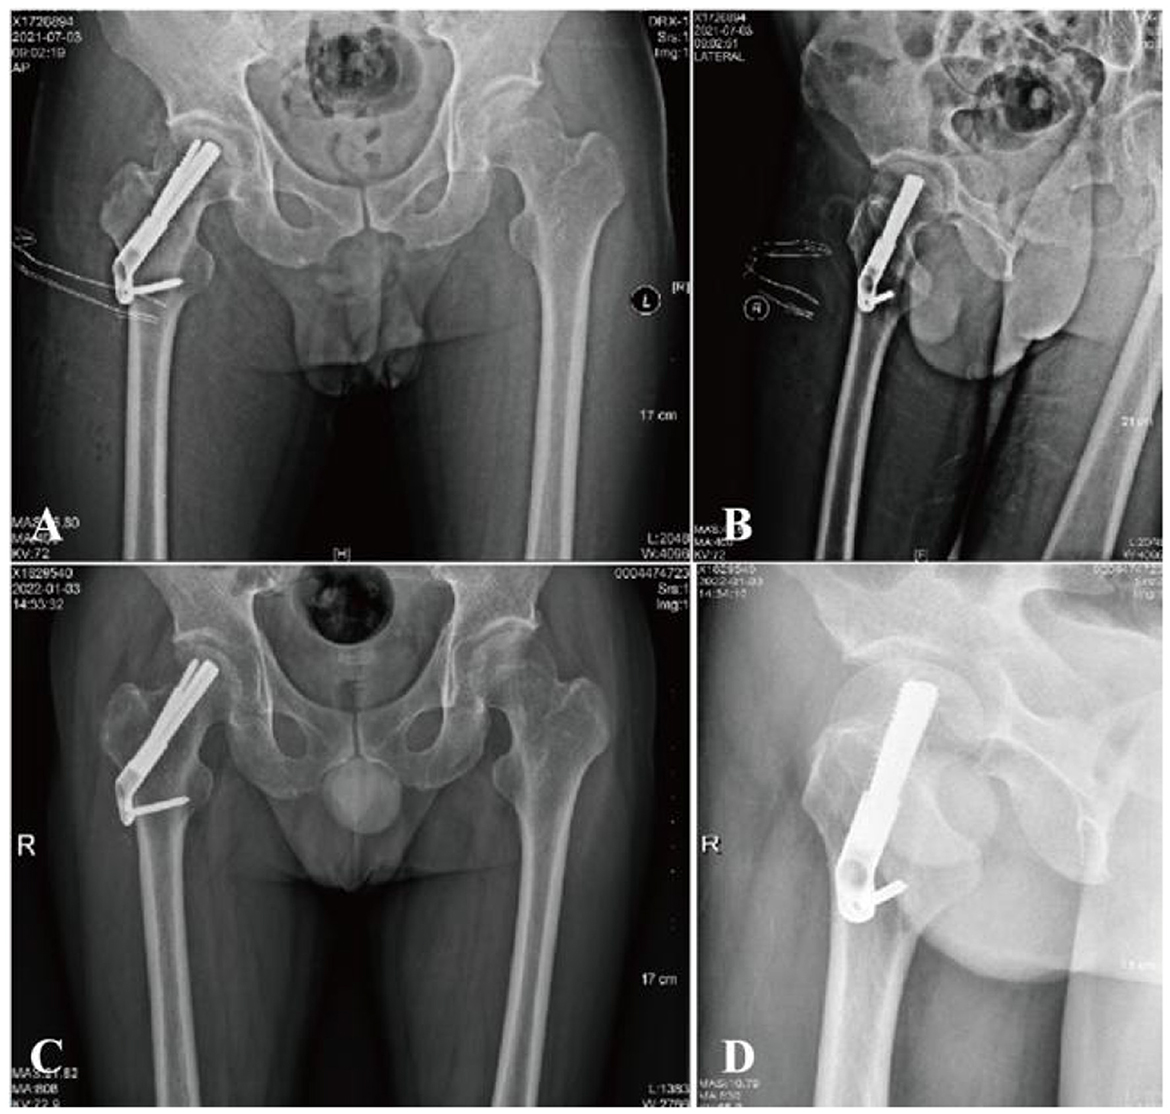

Prior to the final implantation of the FNS, a pre-compression technique was employed. This involved adjusting the sliding distance of the implant before its insertion and limiting the sliding distance to within 5 mm. The specific surgical procedure is shown in Figure 3.

Figure 3

Radiographic and procedural details of FNS implantation in a 41-year-old male with a femoral neck fracture. (A, B) Anteroposterior and lateral views show the position of the implant. The tip of the FNS dynamic bolt was placed 5 mm from the femoral subchondral bone, followed by sequential insertion of the locking head screw and the anti-rotation screw. Due to impaction of the posterior cortex, the sliding distance of the FNS was preoperatively adjusted and limited to within 5 mm before final implantation to prevent excessive femoral neck shortening.